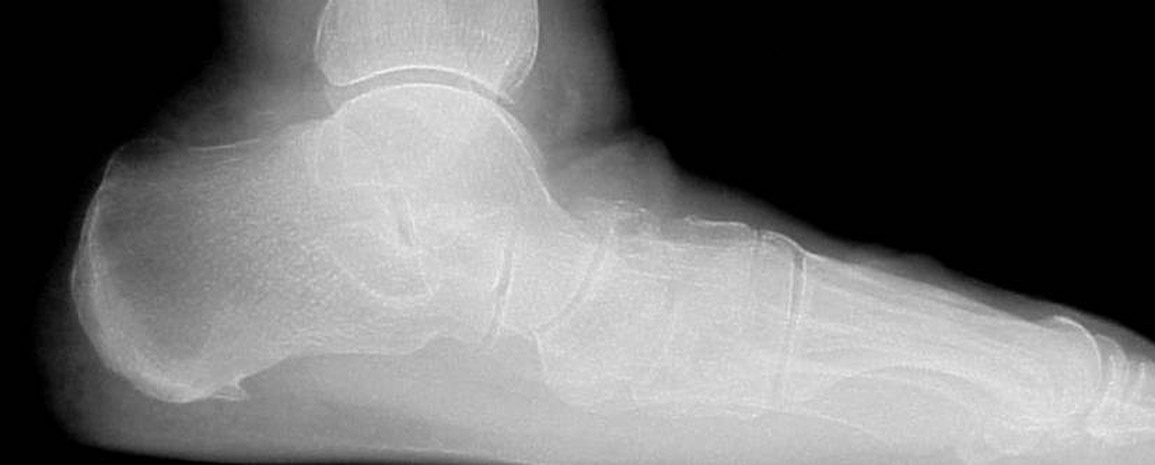

Emphasizing careful assessment of the etiology and underlying contributing factor to subtalar joint instability, this author reviews pertinent conservative and surgical options for treating this conditin in children and adults. There are two forms of subtalar joint instability. It has been recognized as a cause of ankle symptoms secondary to ligamentous injury or laxity of the subtalar joint. This contributes to instability of the ankle as well. Studies show that sectioning of the calcaneal fibular ligament and cervical ligament of the subtalar joint can lead to as much as a 7 mm increase in talar tilt. Surgical repairs to correct lateral ankle instability should include repair or substitution of the calcaneofibular ligament if subtalar instability is a consideration. The other form of subtalar instability is associated with an excessive range of motion with or without pathology. It can be a process of increased motion that leads to minor pathology and muscular fatigue. Alternatively, it may cause a more complex situation of excessive pronatory motion, leading to collapse of the midtarsal joint and global mechanical problems for the foot and lower extremity. For the purposes of this article, I will consider subtalar joint instability as excessive subtalar joint motion or a position that leads to pain and subjective or objective complaints for a patient.

One may appreciate excessive subtalar joint motion early in a child’s life. Often young children will come in with their parents and present with markedly flatfeet and the majority of the collapse originates from the subtalar joint. More often than not, these patients do not have pain but there is a fear of the future ramifications of this position. A full evaluation of the possible pathological etiologies of this condition is necessary. The majority of the children will present these findings as their normal musculoskeletal position. It is debatable whether one should treat a painless/ unstable foot in this situation. Certainly, there are situations in which there is accompanying pain or when findings are so clear that one must institute treatment. However, in the majority of cases involving excessive subtalar joint motion in children, it has been our experience that it is usually best to leave these patients untreated if they are asymptomatic. Over the years of treating professional athletes, it has been our observation that many of the fastest runners and highest jumpers have significant flatfeet that were likely present since childhood. It is hard for us to justify treatment in a child without pain considering the level of achievement of unstable subtalar joints in the professional athletic population. In children who have pain associated with instability of the subtalar joint, utilizing a functional orthotic device or UCBL device can have profound effects on the foot. Children who suffer from pain associated with subtalar joint instability will frequently complain of vague foot/ankle pain, leg pain, “growing pain” and fatiguing quickly when walking or running. By stabilizing the subtalar joint with an external supportive device, clinicians can facilitate more efficient function of the lower extremity and allow for a return to normal activities with reduced pain. It has been our experience that even with the most unstable subtalar joints in children, one can facilitate control with orthotic devices and that nearly all of these patients should receive this treatment alternative initially. However, in some situations, the subtalar joint is too unstable to be controlled by an external orthotic device and one must consider more aggressive measures. When orthotics fail and pain and problems persist, subtalar joint arthroereisis becomes a viable alternative. Over the years, podiatric physicians have frequently utilized arthroereisis in these situations. Few strong, scientific, published reports support the benefits of arthroereisis but those who have the greatest experience with the procedure laud its utility. We have found that absorbable materials may lead to equal success in controlling an unstable subtalar joint without the fear of long-term problems of a metallic implant causing subtalar joint irritation and erosion. Based on the anecdotal experience of those who have had to remove painful metallic arthroereisis implants and reported maintenance of correction, we started using absorbable materials for implantation and have had consistent success. Giannini has reported similar findings on a large series of absorbable implant cases in children.1

It is more common to see adults present with pain and problems associated with subtalar joint instability. In clinicial scenarios that involve minor instability, patients will present with an array of foot and ankle related problems. However, subtalar joint instability can also lead to orthopedic problems affecting the knees, hips and lower back. When the subtalar joint is unstable, the biomechanical effects can be tremendous. The midtarsal joint becomes more unstable and forefoot and rearfoot problems become more pronounced. Common foot and ankle presentations of subtalar instability are posterior tibial tendonitis, anterior tibial tendonitis, plantar fasciitis and forefoot pain commonly associated with lesser metatarsal head overload. Initial treatment for these entities includes improved shoe gear, supportive devices and taping and bracing techniques. Often, the problems of these patients require more permanent support and control, and custom orthotics become necessary. There is a wide array of materials one can utilize for the fabrication of orthotics but it has been our experience that softer orthotics with deep heel seats and medial and lateral flanges are most effective. Not only do these orthotics facilitate comfortable control of these entities, they make the use of forefoot accommodations more tolerable. Additionally, we have found that computer scanning of the foot provides a consistent impression of the foot equal to that of more traditional impression techniques. The computer scanning allows for streamlining of our custom orthotic fabricating process and has tremendously reduced office overhead and costs. When rearfoot and ankle tendon pathologies are present, bracing techniques can have benefits. In the case of early stage tendinitis, there is a wide variety of braces available to control subtalar joint motion in order to reduce the stress on the tendons that are functionally trying to control subtalar joint motion. We prefer to utilize braces that control the subtalar joints while still allowing for somewhat normal shoe wear. The use of a foot/ankle brace with straps is a very effective tool to control these problems and still permit normal shoe wear. Patients can easily utilize these braces in sports activities. Studies have shown an equal benefit of braces to sports taping techniques with better cost effectiveness because of the ability to reuse the brace.2